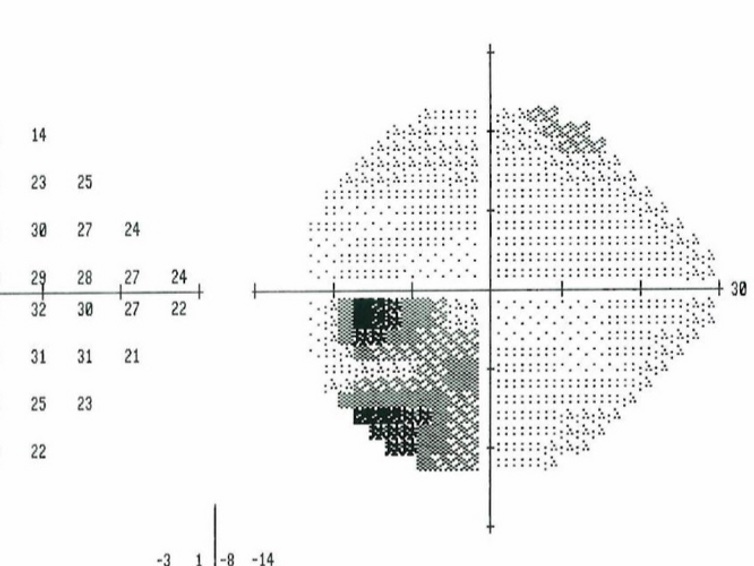

Abstract: Patients with a migraine headache may show visual field defects during and shortly after the migraine. These defects may be the result of transient ischemia and re-perfusion resulting in oxidative stress to the optic nerve much like the proposed pathogenesis for normal tension glaucoma, which has been linked to migraine sufferers. It is therefore prudent to inquire about migraine history during routine eye exams and to run visual fields and RNFL OCTs on migraine patients to monitor for and address any progressive nerve damage.